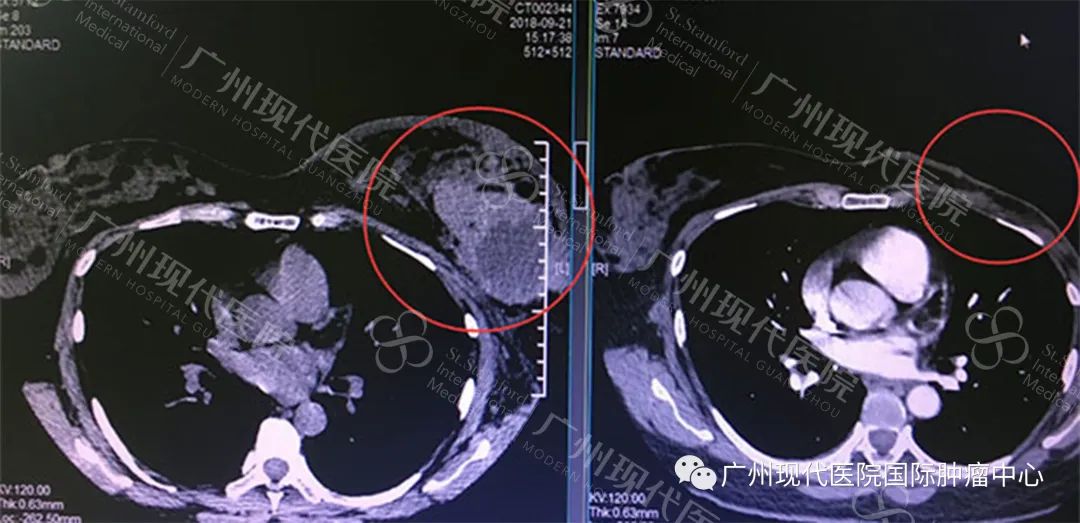

据赵医生介绍,经过一系列的介入、冷冻治疗配合放疗,晒哒的肿块慢慢变小,左乳房的疼痛也逐步减轻,2019年复查时,显示左乳房约12*7.5cm大小的肿块消失了,晒哒的抗癌取得了初步的胜利。

左:2018年9月肿瘤影像,右:2019年6月影像